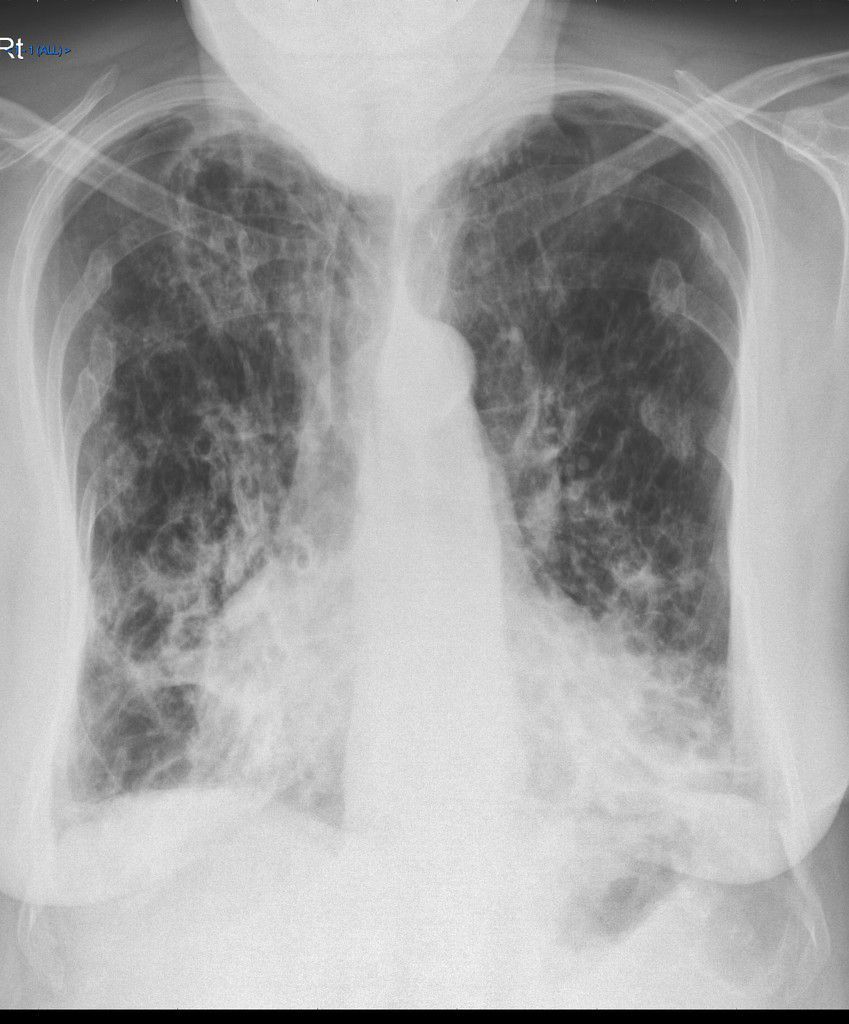

Bronchiectasis refers to abnormal irreversible dilation of bronchial system usually secondary to infections and cystic fibrosis. Majority of cases are idiopathic. Patient with bronchiectasis presents with the history of chronic productive cough, recurrent chest infections, and hemoptysis. The investigation of choice for diagnosis of bronchiectasis is high resolution CT. However, characteristic Xray findings are often demonstrated. -Tram-Track Opacities These are usually seen in cylindrical bronchiectasis. -Air-Fluid Levels It is demonstrated in cystic bronchiectasis. -Increased Bronchovascular Markings -Ring Shadows of Bronchi -Ill-defined pulmonary vasculature It indicates peribronchovascular fibrosis. Reference: https://radiopaedia.org/articles/bronchiectasis